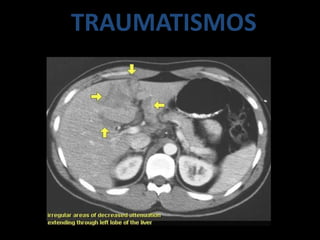

TRAUMATISMOS

• LAS LESIONES TRAUMATICAS PUEDEN SER :

– CONTUSIONES

– DESGARROS

– HEMATOMAS

– ROTURAS

– LACERACIONES

• EN TC :

CONTUSION SIN ROTURA SE MANIFIESTA COMO

IMAGEN HIPODENSA EN CONTRASTADA ESTO

PUEDE SER POR EDEMAS Y HEMORRAGIAS

MICROSCÒPICAS

DESGARRO HEPATICO

TRAUMATISMO: INJURIA HEPATICA